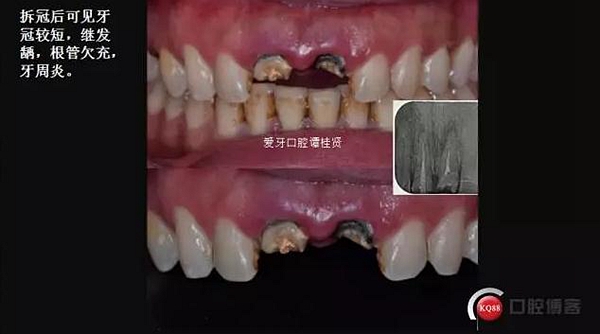

口內(nèi)檢查:很輕易就取下牙冠,均為殘冠殘根且繼發(fā)齲,#21尤為嚴(yán)重,已到齦下,牙周探診1.5mm,X線檢查:根尖陰影,欠充。

診斷:#11#21殘根,繼發(fā)齲,輕度牙周炎。

二診

三診 牙周牙髓聯(lián)合治療